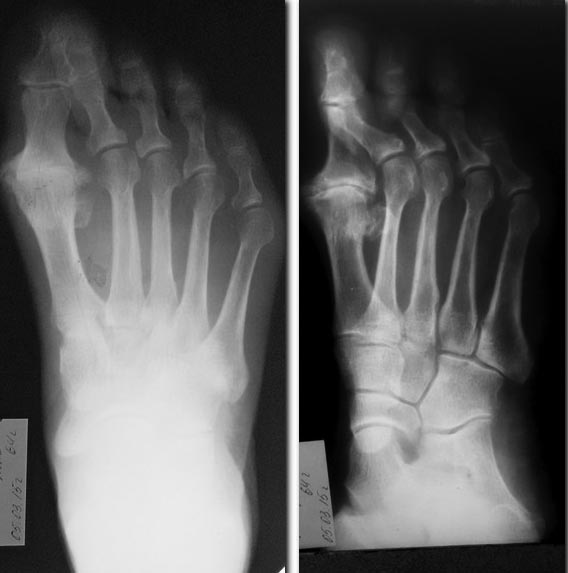

Так получается, что нужно завтра прооперировать больную. Планирую

операцию: Лапидус.

Может быть нужна другая операция? Возраст 63 года.Спасибо.